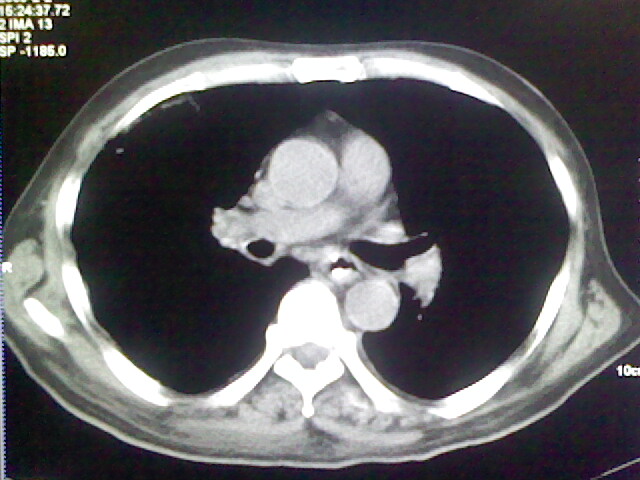

男,70岁,脑出血,长期卧床,左侧背部可触及肿块

右肺病灶考虑炎症性。

右肺病灶考虑炎症性

考虑右肺及左肺下叶炎症。

右肺及左肺下叶炎症。

右侧肺部见片状密度增高影,边缘模糊。考虑炎症。另食管壁增厚。

右肺上叶前段病呈楔形,其尖端指向肺门,考虑肺动脉栓塞可能性大.